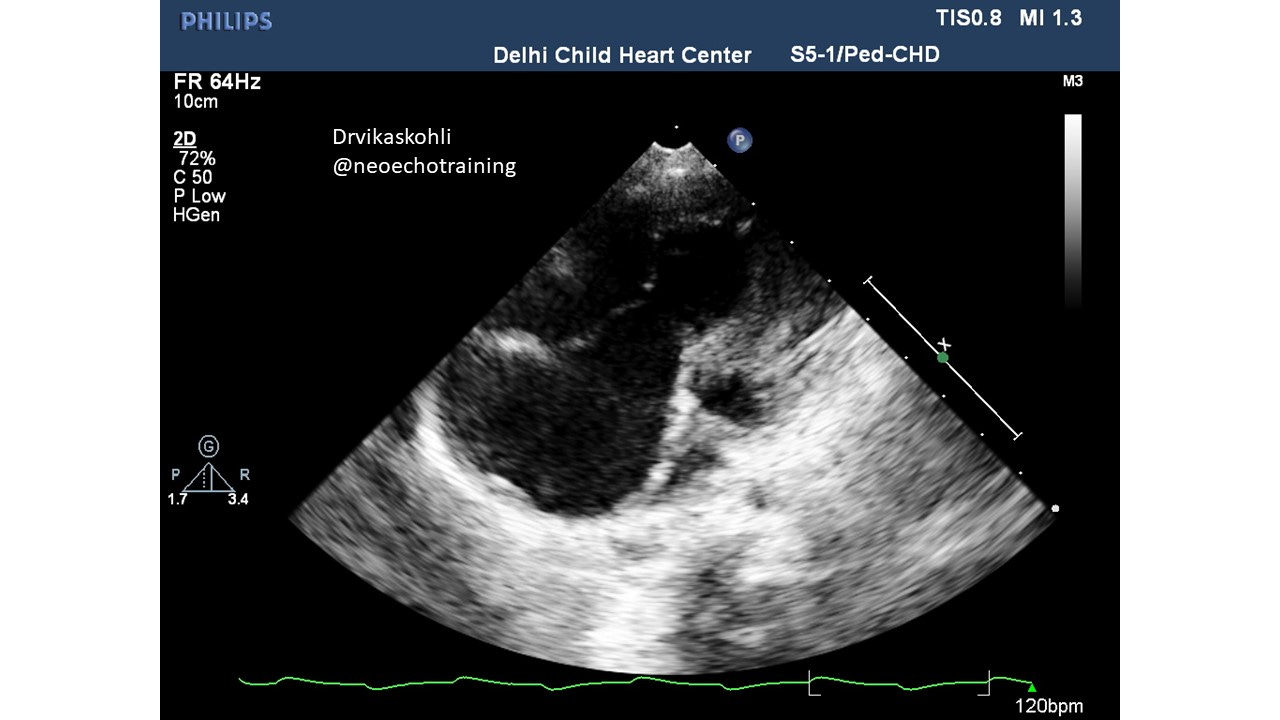

a). The Tricuspid Leaflets are HUGE

b). The leaflets are seen septal (along the septum and the Anterior which is along the free wall).

c). The Septal leaflet if you look carefully ( and in the picture below) is stuck to the septum and moves only near the apex of the RV:

There are other leaflets: anterior and posterior. They may also be abnormal. They could be displaced or could be abnormally large sail-like.

This is associated with severe TR which is normal pressure TR.

The RV from the true tricuspid attachment to the new septal leaflet attachment is referred to as Atrialized RV.